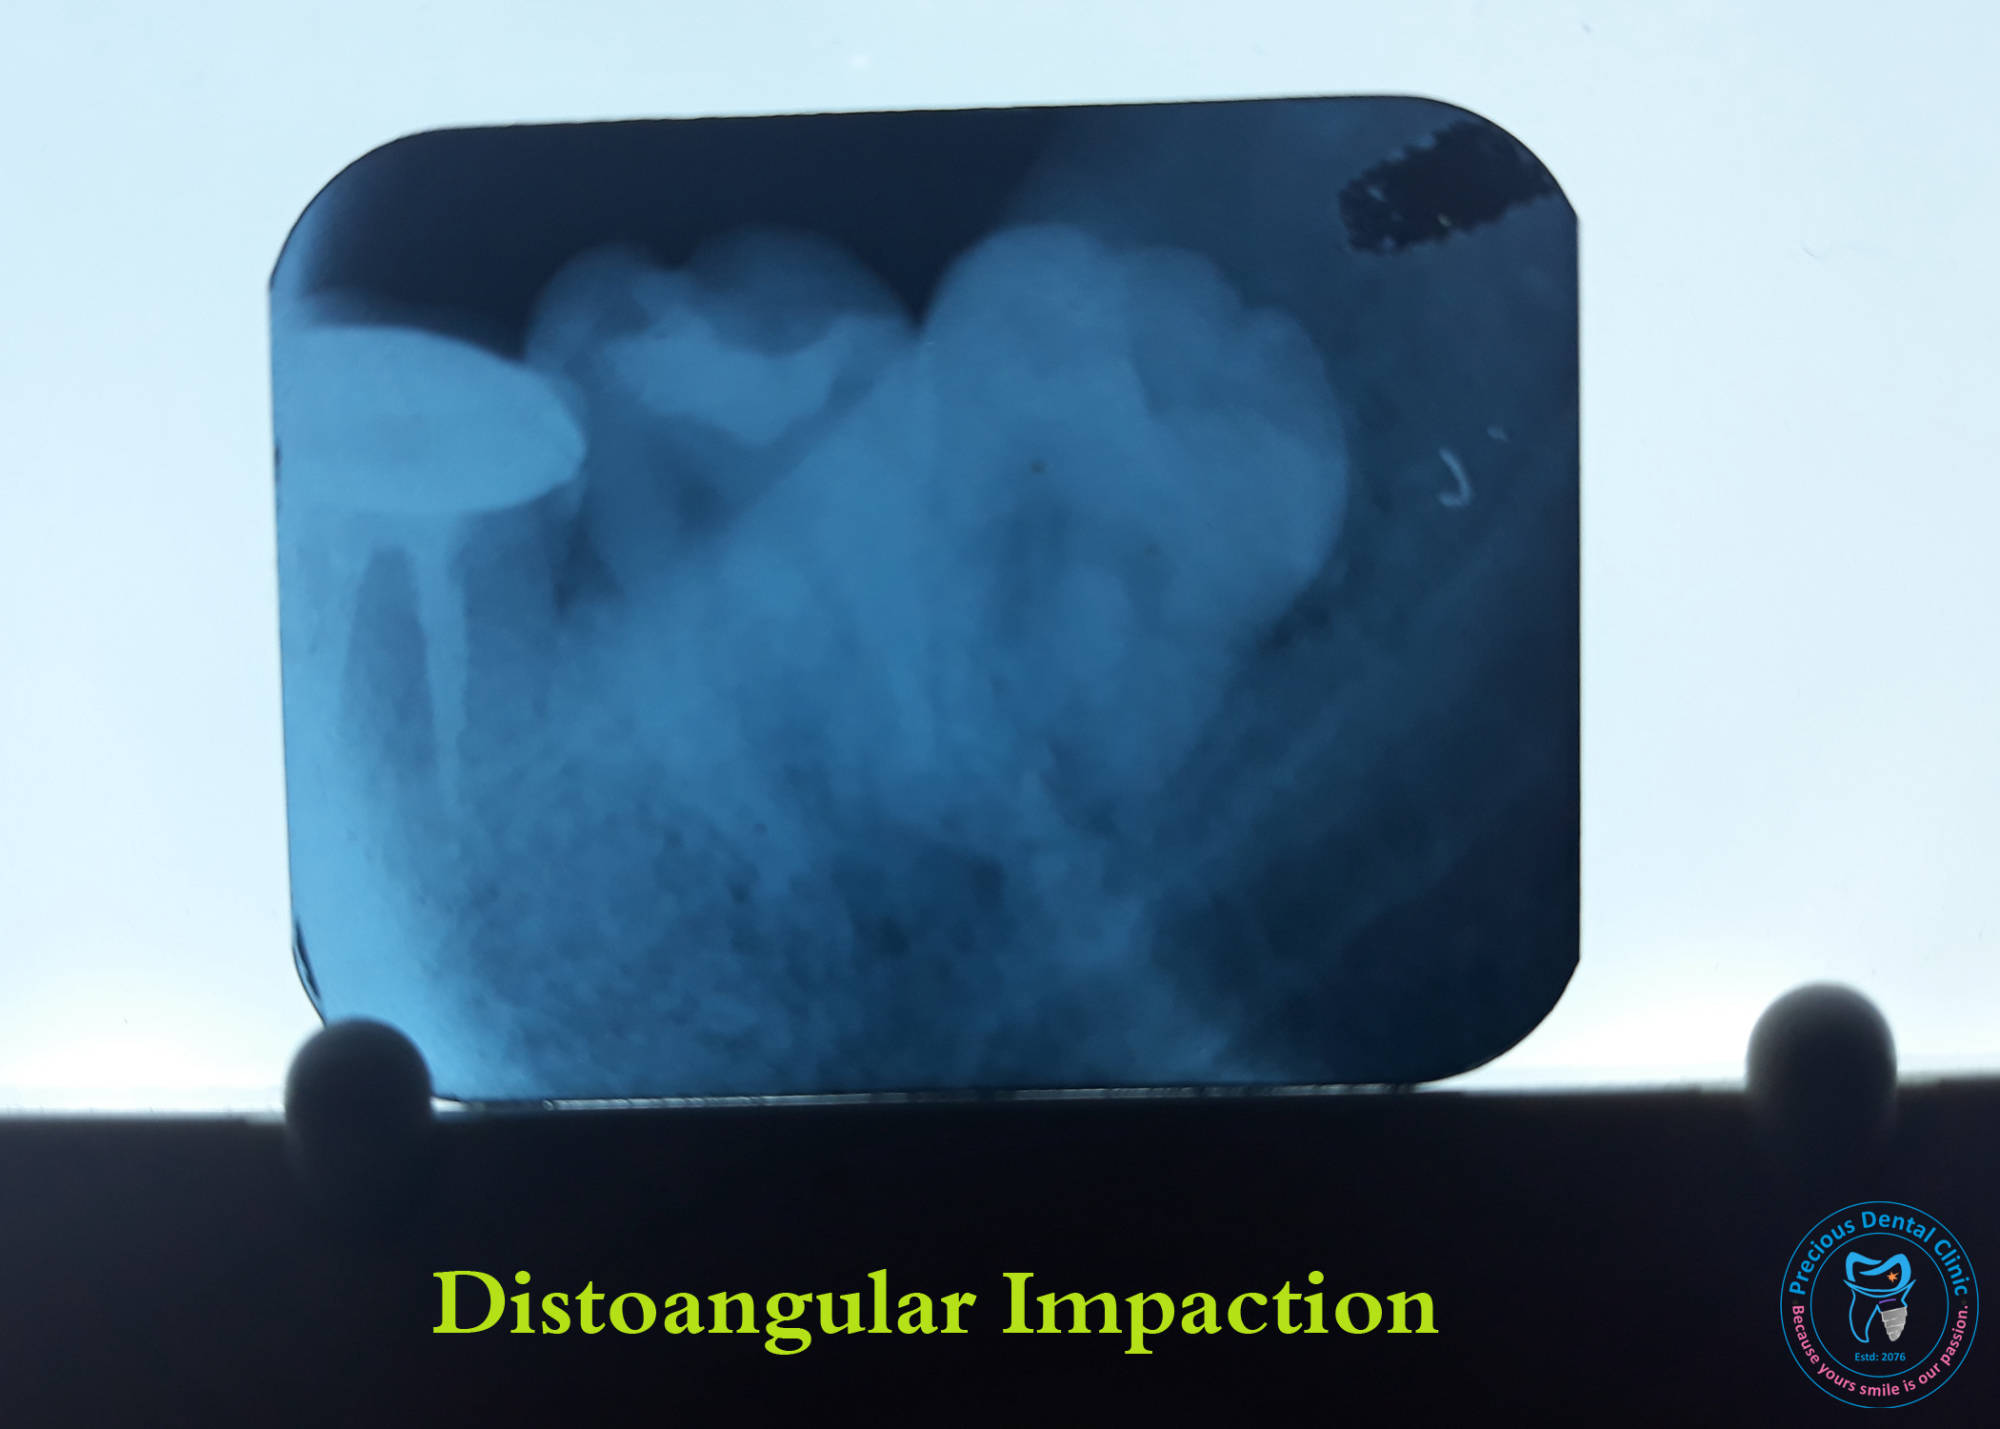

Dental Stomattis Distoangular impaction

Distoangular impaction Dog Bite

Hematoma Horizontal impaction

Horizontal impaction Lip Injury